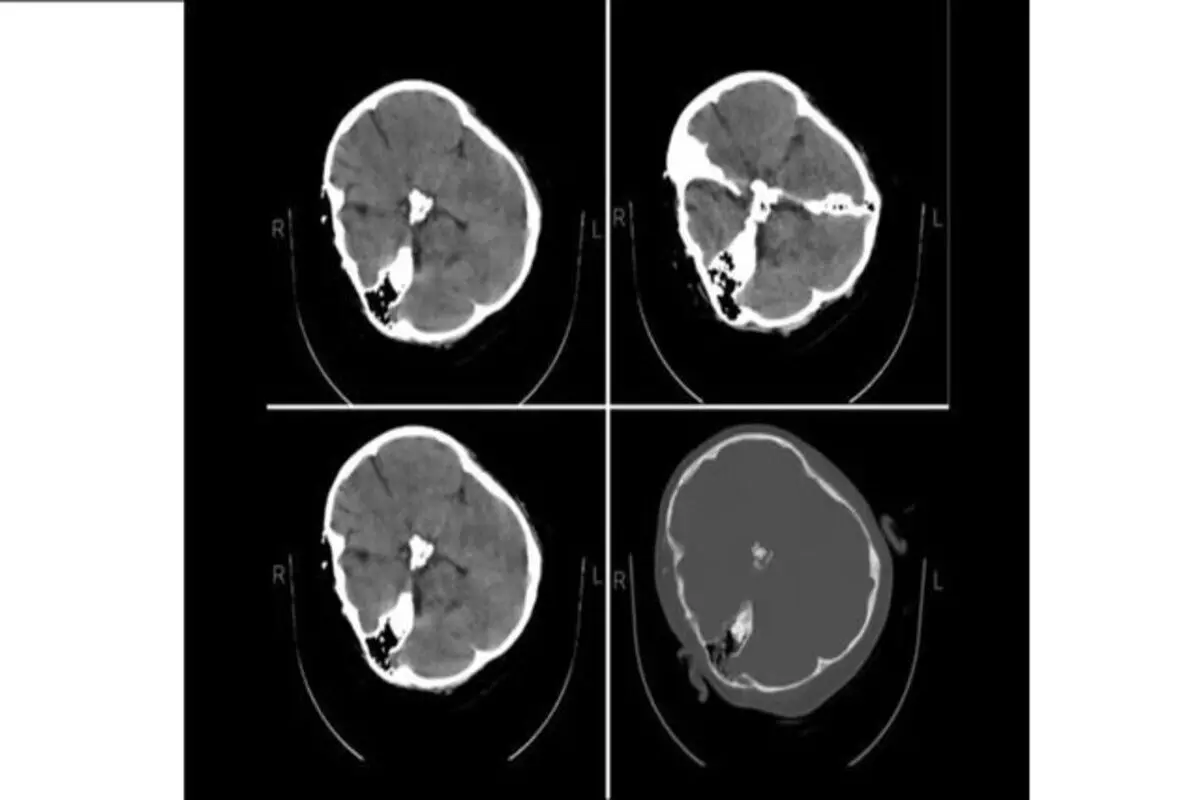

هیچ شواهدی از خونریزی مغزی در تصاویر سی تی اسکن «مهسا امینی» دیده نمیشود

به گزارش پارسینه ؛ در بیانیه متخصصین نرورادیولژی هیأت بورد رادیولوژی وزارت بهداشت که در پاسخ به استعلام ریاست نظام پزشکی صادر شده، آمده است: «با توجه به استعلام ریاست نظام پزشکی، متخصصین نرورادیولژی هیات بورد رادیولوژی وزارت بهدشت، پس از بررسی تصاویر سیتی اسکن مغز مرحومه مهسا امینی اعلام میدارد در سیتی اسکن که بهصورت فیلمبرداری از، مانیتور تهیه شده است، خونریزی در پارانشیم مغزی، خونریزی اپیدورال و سابدورال دیده نمیشود.»

تصویر سی تی اسکن یه شخص دیگه هستش.دروغه تصویر